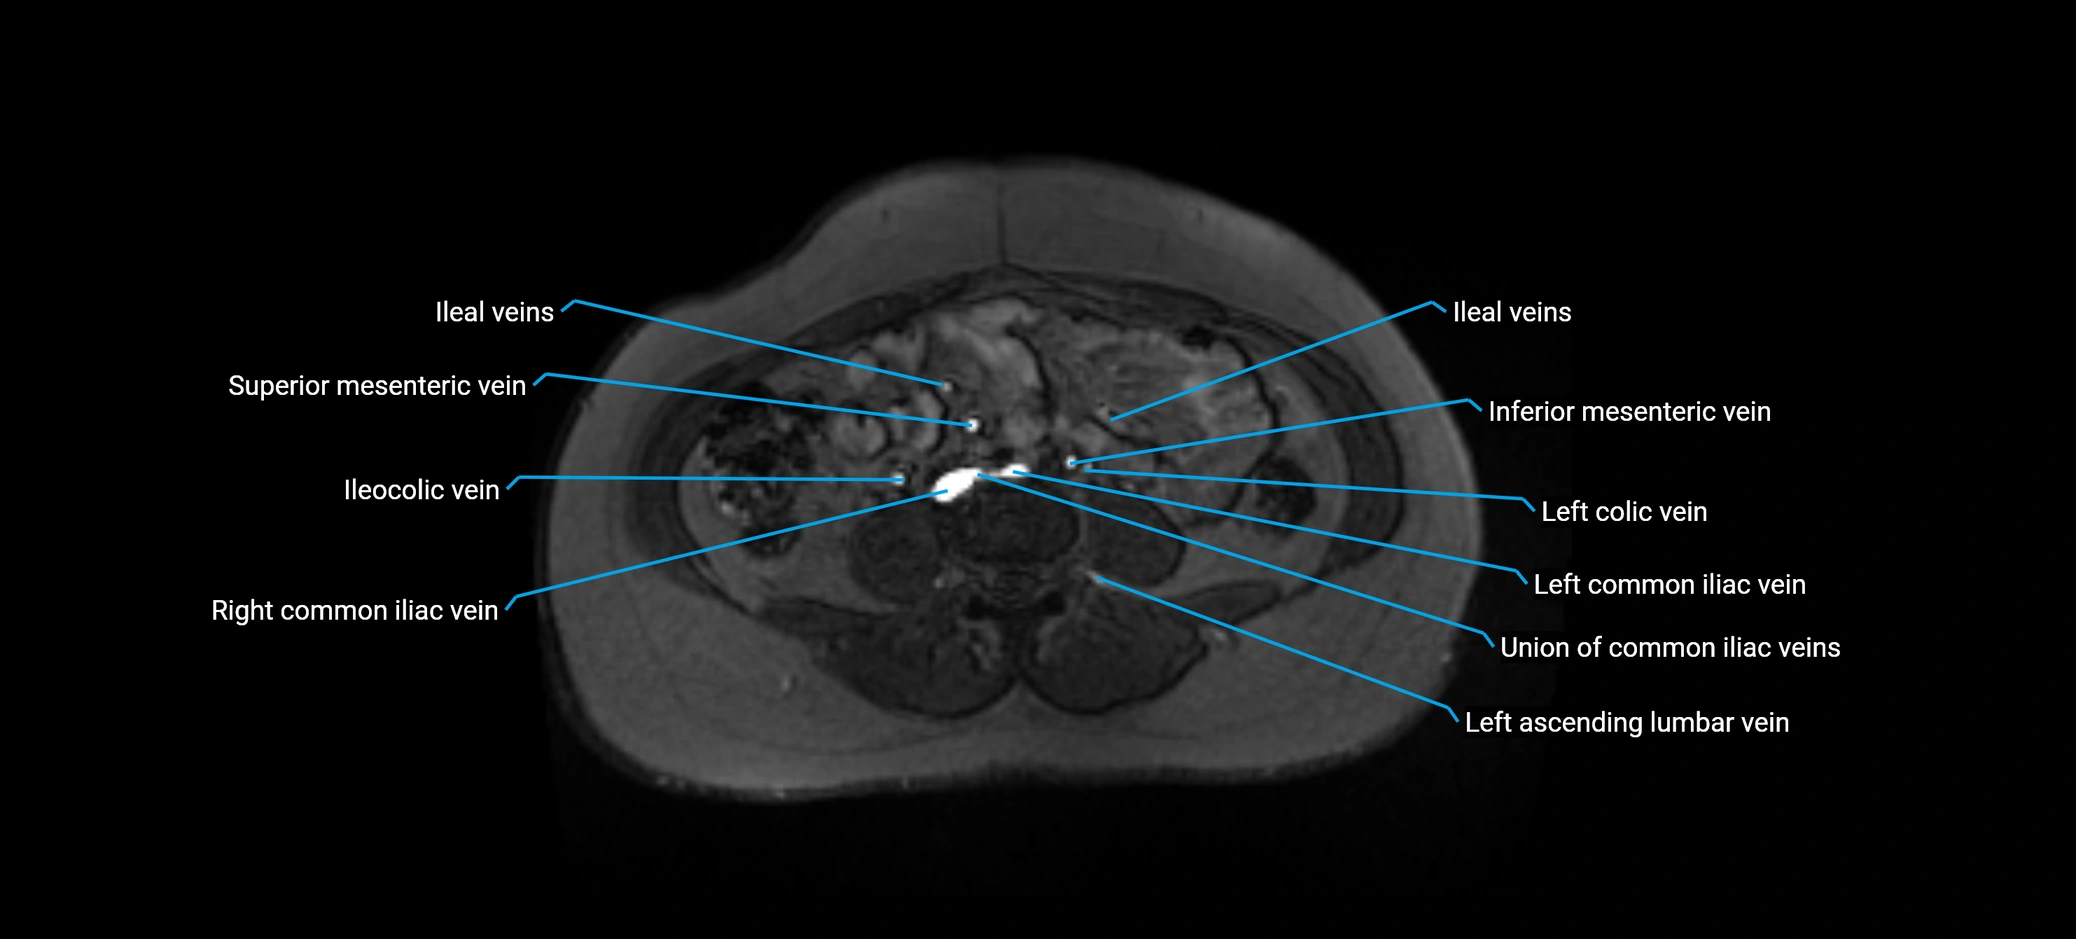

MRI image

image